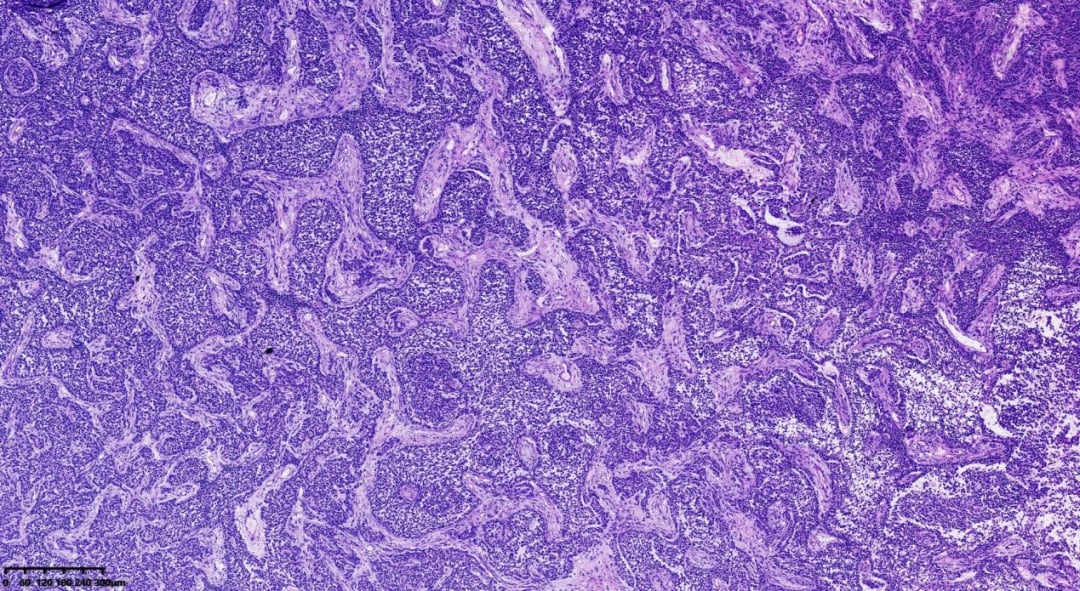

在显微镜下,肿瘤细胞呈现出多种独特的排列模式,为病理诊断提供了关键依据:

肿瘤呈巢状、岛屿状分布,细胞较小

肿瘤呈梁状、条索状分布

肿瘤弥漫性分布,肿瘤细胞胞质相对较少,呈单一表现

- 组织病理学:瘤组织排列模式多样,同一肿瘤内可能出现多种结构,包括弥漫性、结节状、小梁状、条索样、岛屿状、滤泡状、波浪状、脑回样及肉瘤样。少数病例可见囊性变区域,甚至形成假乳头。瘤细胞通常胞质稀少、淡染,大小相对一致,界线不清,呈卵圆形或多边形,细胞核轮廓不规则,可见核沟或呈咖啡豆状。核分裂象通常较少见,75%的病例中每10个高倍视野(HPF)少于3个。